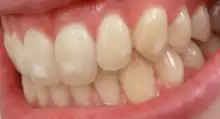

It appears as a range of visual changes in enamel[4] causing degrees of intrinsic tooth discoloration, and, in some cases, physical damage to the teeth. The severity of the condition is dependent on the dose, duration, and age of the individual during the exposure.[1] The "very mild" (and most common) form of fluorosis, is characterized by small, opaque, "paper white" areas scattered irregularly over the tooth, covering less than 25% of the tooth surface. In the "mild" form of the disease, these mottled patches can involve up to half of the surface area of the teeth. When fluorosis is moderate, all of the surfaces of the teeth are mottled and teeth may be ground down and brown stains frequently "disfigure" the teeth. Severe fluorosis is characterized by brown discoloration and discrete or confluent pitting; brown stains are widespread and teeth often present a corroded-looking appearance.[1]

| Questionable | 1 | The enamel discloses slight aberrations from the translucency of normal enamel, ranging from a few white flecks to occasional white spots. This classification is utilised in those instances where a definite diagnosis is not warranted and a classification of 'normal' not justified |

| Very Mild | 2 | Small, opaque, paper white areas scattered irregularly over the tooth but not involving as much as approximately 25% of the tooth surface. Frequently included in this classification are teeth showing no more than about 1 – 2mm of white opacity at the tip of the summit of the cusps, of the bicuspids or second molars. |